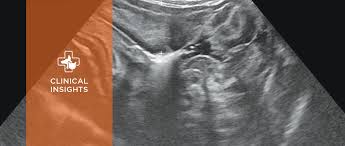

Can Ultrasound Detect Cancer In Cats : Cancer In Cats Symptoms Treatment Purina : Lymphoma is a cancer of lymphocytes, which are white blood cells that are part of the immune system.. Lymphoma is a cancer of lymphocytes, which are white blood cells that are part of the immune system. Without early detection and proper treatment, the prognosis for a cat with intestinal cancer is poor, and the condition can be fatal. This means the symptoms and signs of feline cancer are also varied and can be difficult to recognize. An ultrasound can show us if your furhead has a tumor, where it is located in the bladder, and if surgery carries a fair to good prognosis. Rozanski proposed that a focused cardiac ultrasound (fcu), an abbreviated echocardiogram using equipment already available in a practice, could screen and determine if a cat should receive a.

Feline Lymphoma Clinician S Brief from files.brief.vet Diagnosing cancer in cats veterinarians rely on many of the same diagnostic tools used in human medicine, including blood work, radiographs, ultrasounds, mris, cat scans and pet scans. Lymphoma is a cancer of lymphocytes, which are white blood cells that are part of the immune system. Ultrasound also allows the doctor to look for the presence of masses that may indicate cancer; A cat with gastric lymphoma can be expected to survive an average of six months with chemotherapy, although a cat that initially responds favorably to chemotherapy can be expected to survive for over a year, on average. It can detect abnormal tissues, growths, and cysts and give a suspicion of cancer based on how those images look. However, there are instances when blood tests can help us diagnose cancer and also help us provide you with the most information about your dog's or cat's condition. Knowing the signs of cancer in cats and things you can do to watch for cancer can literally save your cat's life. An ultrasound can find dense areas of tissue such as tumors or.

While it can't diagnose cancer, it can detect the abnormal tissues that may possibly be cancerous.

And because cats have a tendency to mask illnesses, it can be harder to detect. Bladder cancer in cats fortunately, this type of tumor is very rare in cats. Lymphoma is a cancer of lymphocytes, which are white blood cells that are part of the immune system. For many types of cancer in dogs and cats, it is common for routine blood tests such as the complete blood count and chemistry panel to be completely normal. Ultrasound uses sound waves and their echoes to produce pictures of parts of the body. However, if a cat shows symptoms of a major uti without resolution after treatment, it would be important to do additional tests (such as an ultrasound) to rule out cancer. Ultrasounds that detect blood vessels can also find narrowed vessels or blockages to blood flow. While it can't diagnose cancer, it can detect the abnormal tissues that may possibly be cancerous. Remember, cats are really good at hiding illness. Rozanski proposed that a focused cardiac ultrasound (fcu), an abbreviated echocardiogram using equipment already available in a practice, could screen and determine if a cat should receive a. Ultrasound is often one of the first line tests in the detection of cancer. Cats are good at hiding symptoms, and it can be hard to recognize signs of cancer. Ultrasound can detect illnesses like diseases of the kidney such as polycystic and chronic renal disease, liver diseases like hepatitis and liver flukes, pancreatitis, gastrointestinal diseases, bladder problems like cystitis, cancer, and pregnancy.